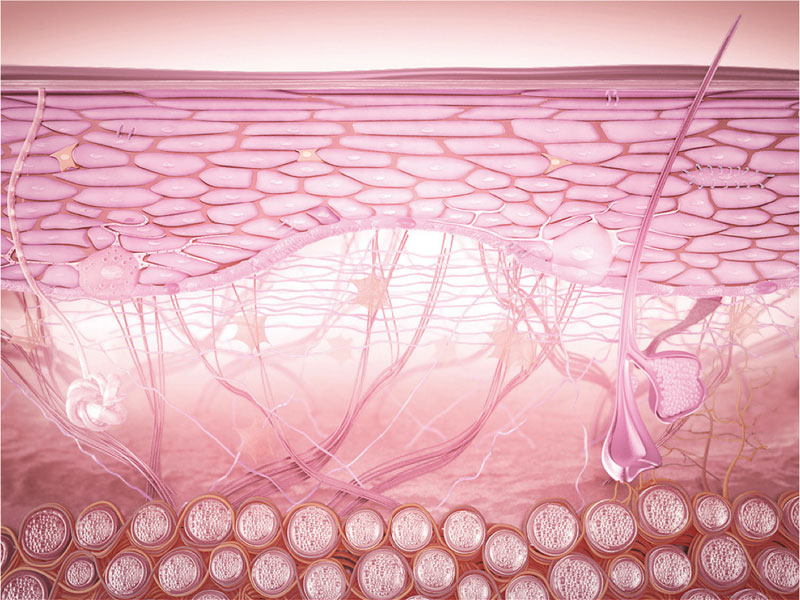

La epidermis del contorno de ojos es muy poco espesa y la dermis también es muy pobre en fibras, principalmente en fibras de colágeno y en fibras de fibrilina, principal constituyente de las fibras elásticas.

El tejido subdérmico también es muy diferente a la hipodermis habitual porque no contiene células adiposas. Y la escasez de glándulas sebáceas conlleva una débil producción de sebo y una capa hidrolipídica muy fina y poco protectora.

La piel del contorno de los ojos está muy solicitada: los párpados están en movimiento en cada una de nuestras expresiones con el fin de asegurar una hidratación permanente de la córnea, extendiendo en la superficie el líquido segregado por las glándulas lacrimales.

Las opsinas son proteínas fotorreceptoras encargadas de absorber la luz. Tres tipos de opsinas participan en la absorción de esta luz azul: la 1 que trata la luz azul-violeta y está presente principalmente en las membranas de los queratinocitos, en la capa superior de la epidermis. La opsina 2, receptora de la luz azul verde, está presente al mismo nivel; y la opsina 3, sensible a la luz azul, está instalada de manera más difusa en la piel.